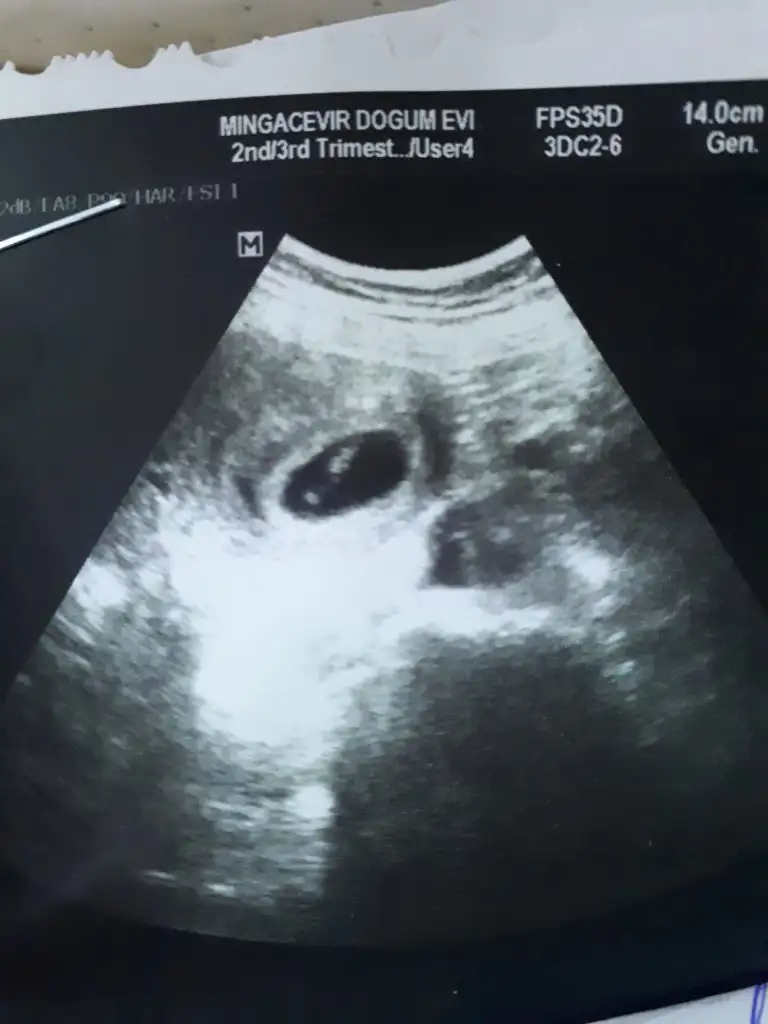

Merhaba ben 13+5 iken karından muayene oldum cinsiyet konusunda yardımcı olur musunuz